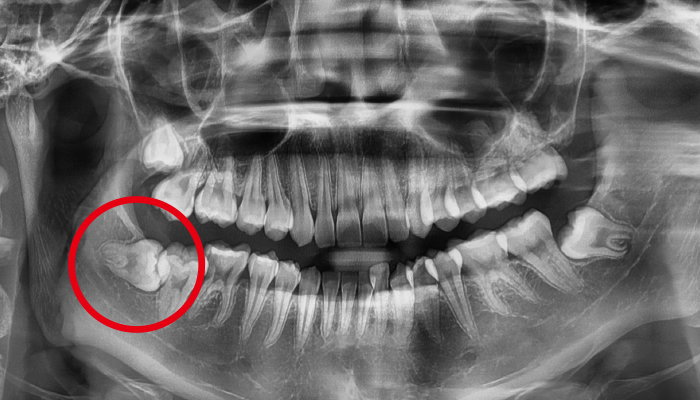

사랑니 발치 전후 사례

• 치료전

치료후